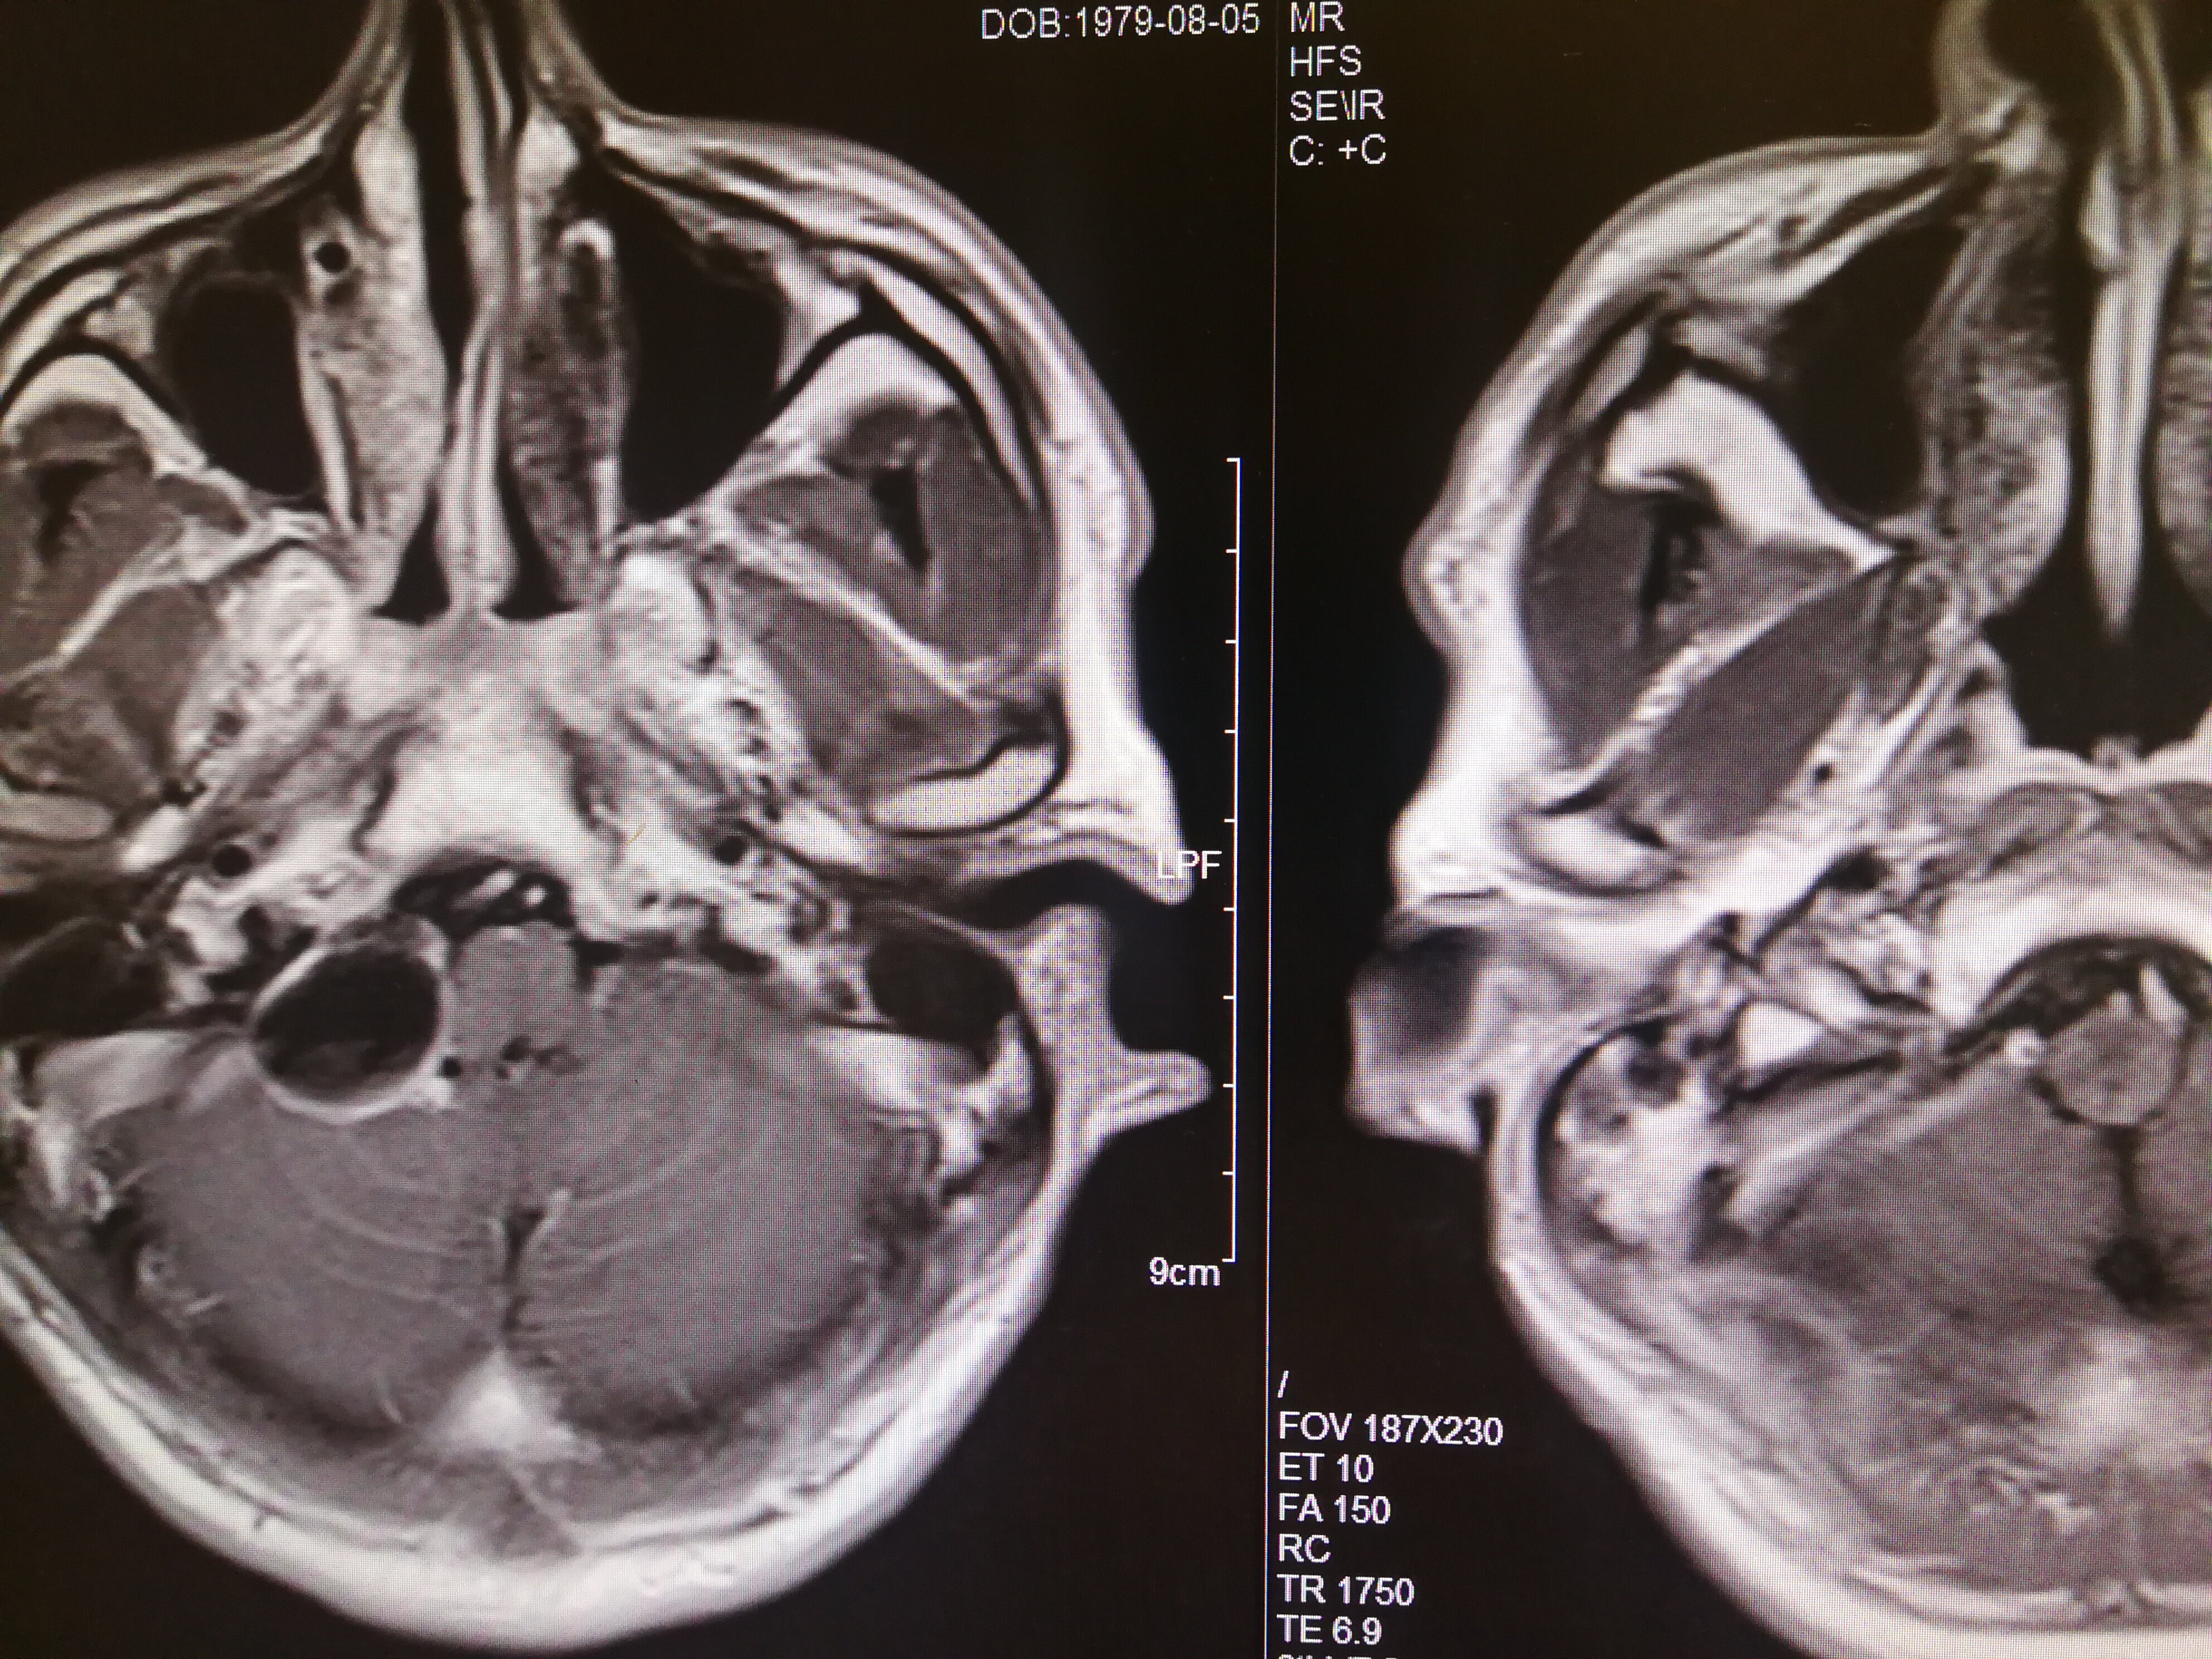

手术治疗听神经瘤是最主要的治疗方式,目前听神经瘤的手术已经非常成熟,只要没有明显的手术禁忌症首先应考虑手术治疗,并要求在电生理监测条件下完成手术,这样可以最大限度地保护面神经功能。以下是几例我们做的听神经鞘瘤手术前后核磁共振片子对照,除手术后听力不能恢复外,没有面瘫,脸部麻木,吞咽困难等颅神经症状,也无其他较明显的手术并发症发生。